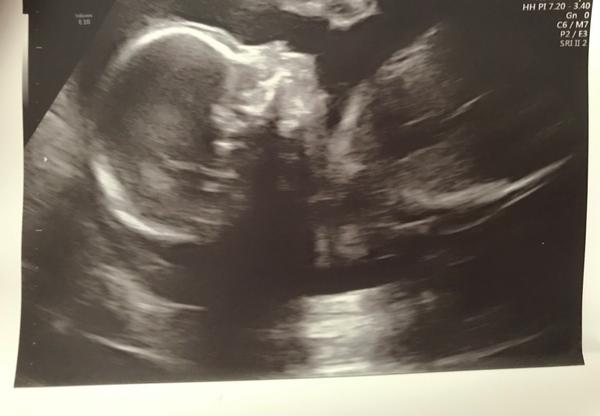

Malá bradička nebo nevyvinutá spodní čelist u plodu

Ahoj maminky... Je tu někdo komu doktor na UTZ řekl že jeho mimčo má malou bradu nebo nevyvinutou spodní čelist? :(

Ano já 🙂 byla jsem jsmem kontrole, kde hlavně zkoumali, jestli tam není přidružený rozštěp patra nebo něco dalšího. Naštěstí se nic takového nepotvrdilo, nicméně menší bradička zůstává. Ale mám to trochu i rodové.